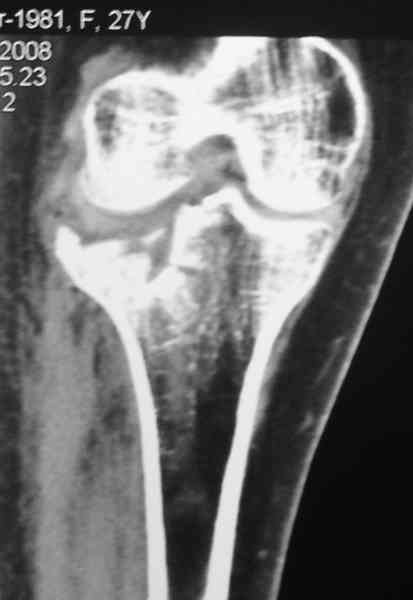

Есть ли возможность сделать КТ?

К большому сожалению КТ пока на ремонте, как запустять, сразу сделаю. Спасибо.

Уважаемый Абдурашид. Если нет противопоказаний , то из оперативных способов, я бы рекомендовал следующие: Полное замещение наружного мыщелка аллотрансплантатом либо открытая репозиция с элевацией и замещение дефекта ауто или аллокостью. В Ваших условиях , я бы рекомендовал второй способ. Во-время элевации необходимо разъединить фрагменты со стороны сустава ( надсечь скальпелем по линиям перелома, а затем тонким остеотомом их разъединить. При помощи долота произвести неполную остеотомию ( захватите не менее 1,5 - 2 см губчатой кости и поднять фрагменты, визуально отрепонировать и фиксировать 2-3 спицами. Дефект заместить костным ауто или аллатрансплантатом. Окончательная стабилизация пластиной ( лучше с угловой стабильностью, либо АВФ - позволит спокойно устранить угловую деформацию.

Недавно поступила больная через 1,5- 2 месяца.

Я согласен с мнением доктора Соломина, что необходимо выполнить СТ. Это поможет Вам не только определить степень повреждения твёрдых тканей, но и увадеть степень сращения. Без СТ не возможно планировать дальнейшую тактику лечения.